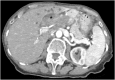

Direct transpapillary resection of a left hepatic duct polyp